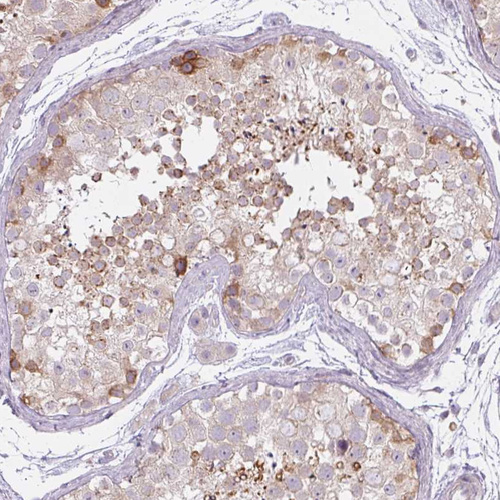

Immunohistochemical staining of human lymphoid tissues shows moderate positivity in nuclear membrane in non-germinal center cells in addition to moderate cytoplasmic expression.